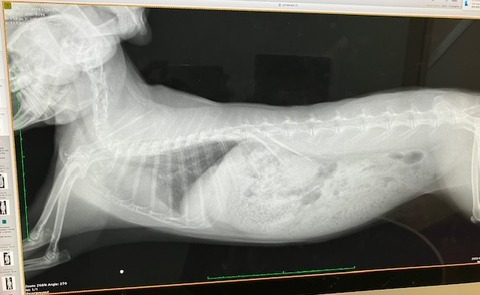

レントゲンでは...

歯根の問題はなさそうですが、鼻の奥の方(?)

堆積物か何か、何かがあるかもしれない、みたいな話でした。

どこかすぐ忘れるから指さし撮影(^_^;)

鼻涙管の通り道ではないので、排除となると外部から穴をあけるらしい…。

詳細はCTなどを用いて調べられる。

まあ、強いていえば、という感じでしたし、ひとまず経過観察です。

胸の方は

こちらも大きな問題なさそう、ですが、

心臓の輪郭がはっきりしてない箇所があります。

(向かって右上、白くモヤってるところ)

こちらは、ちょうど3年前、

去勢手術の術前検査で撮影したレントゲンがあったので比較すると、

ほとんど変化がありません。

肺の一部が弱ってる(しぼんでる?)のかなと。

(うさぎは肺が6個やったっけか?

1つ2つ機能しなくなっても生活に支障はない、とか…

過去の記憶ですが💦)

また、生まれつき(先天性)かも。

※緊急性の高い呼吸困難の症状が出ていない場合での見解です※